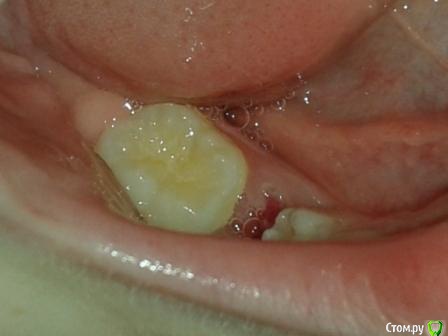

Через год начал прорезываться зуб, стоящий рядом с пролеченным. Прорезался и… наклонился. Теперь он ушел в наклон с одной стороны, закрывая при этом часть поверхности 5-ки. Наплыла десна, но не критично. С одной стороны зуб полностью вырос, с другой – в десне.

Обратились к терапевту. В лечении зубы не нуждаются, но высказала мнение, что нужно показаться ортодонту. Объяснила нам ситуацию: зуб вскоре закроет непрорезавшуюся 5-ку, и постоянный зуб под 5-кой не прорежется.

Прибыли к ортодонту. Снимок она получила за месяц до нашего визита. Лечение обдумала заранее. Пять минут осмотра и вердикт – сегодня делаем оттиски, оплачиваете половину стоимости лечения, и ставим пластинку, которую необходимо носить 1,5 года. Ребенок закусывает щеку на той стороне, где наклонен зуб. Ничего внятного не услышала на это счет.

Прилагаю снимки. Один до того, как прорезался наклоненный зуб. Второй - после его прорезывания и лечения зуба с анкилозом. Прошу прощения за качества некоторых снимков.